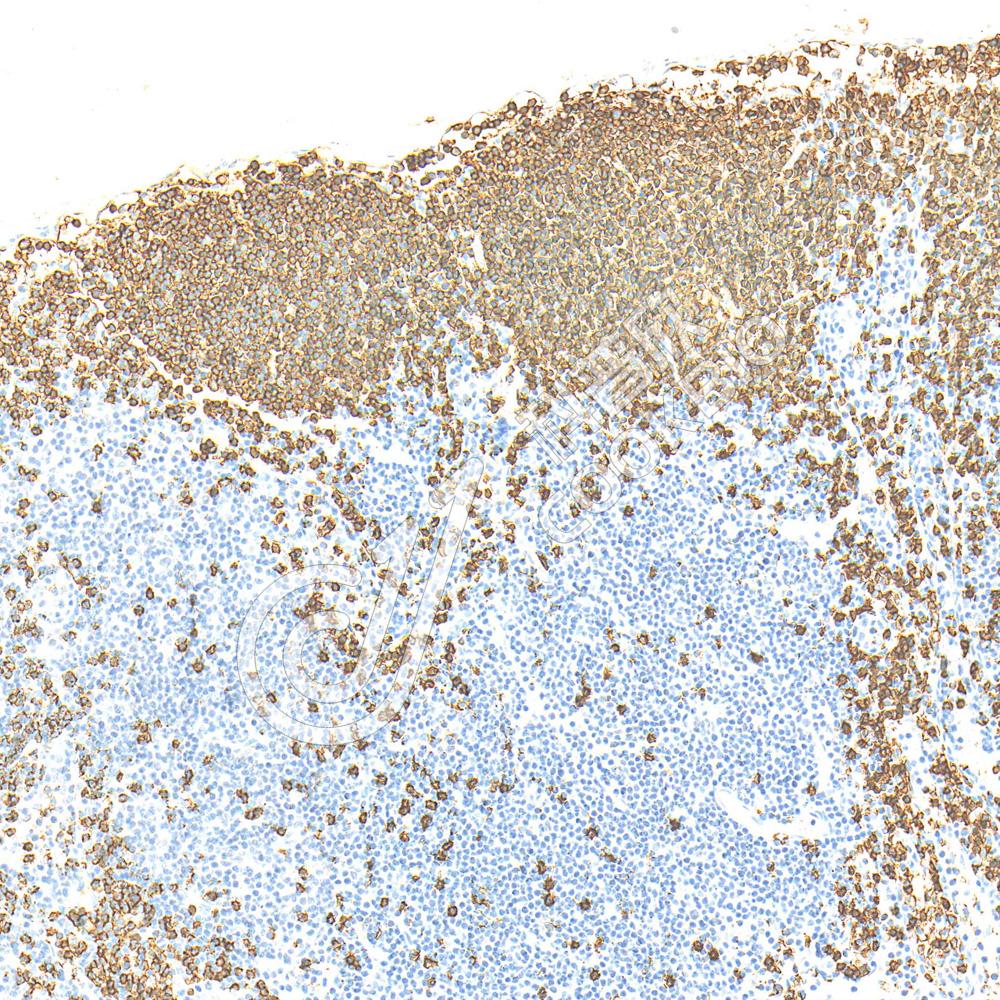

IHC检测CD45蛋白(货号 K133198).

样品: 小鼠肺, 4%多聚甲醛 (货号KSG1101) 固定12-24小时.

抗原修复: 柠檬酸抗原修复液(干粉, pH 6.0) (KSG1201), 高压锅均匀喷气计时2分钟.

—抗: 1: 2500稀释, 4℃ 孵育过夜.

二抗: S-vision免疫组化多聚二抗(山羊抗兔),即用型 (货号KB3906), 室温孵育20分钟.